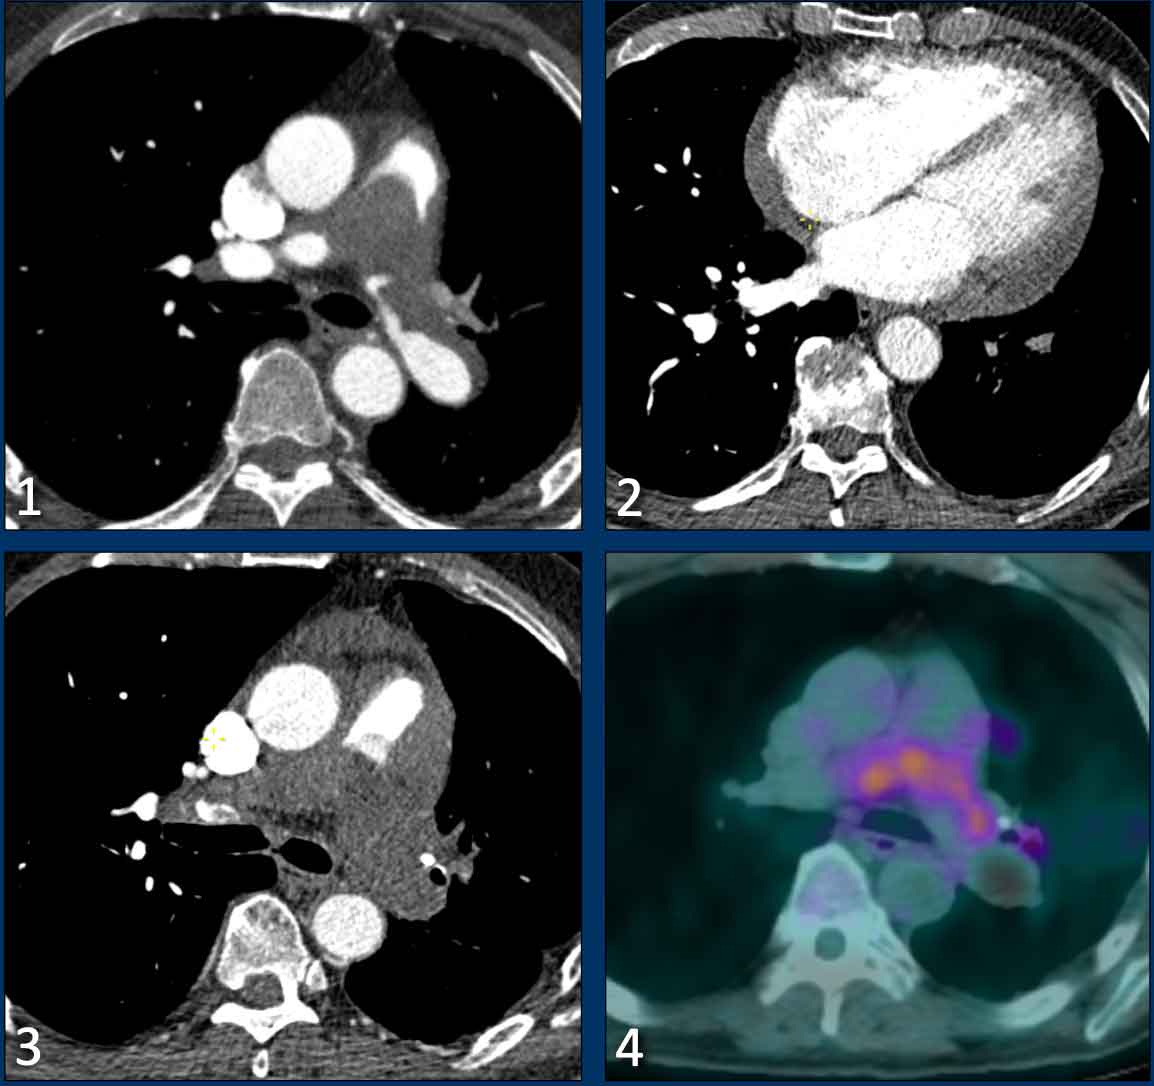

Pulmonary artery sarcoma

The most important mimicker of chronic thromboembolic disease is pulmonary artery sarcoma, a rare primary malignant tumor arising from the vessel wall.

It typically presents as a central filling defect within the pulmonary artery and may initially be mistaken for thrombus.

Although signs of flow obstruction and right heart strain may be present, right ventricular hypertrophy is often absent due to the rapid progression of the tumor.

Imaging features suggestive of a pulmonary artery sarcoma include:

• An expansile intraluminal mass, which may have an extravascular infiltrative component.

• Involvement of the pulmonary valve and/or right ventricular outflow tract.

• Absence of ancillary signs of chronic thromboembolic disease.

• Enhancement after contrast administration.

• FDG-PET avidity (frequent, but may be low or absent).

• Growth despite anticoagulant therapy.

Images

• There is a large filling defect within the central pulmonary arteries.

• Notably, there is no distinct right ventricular hypertrophy or dilatation.

• Progressive size despite anticoagulation therapy.

• Metabolic activity on FDG-PET imaging.